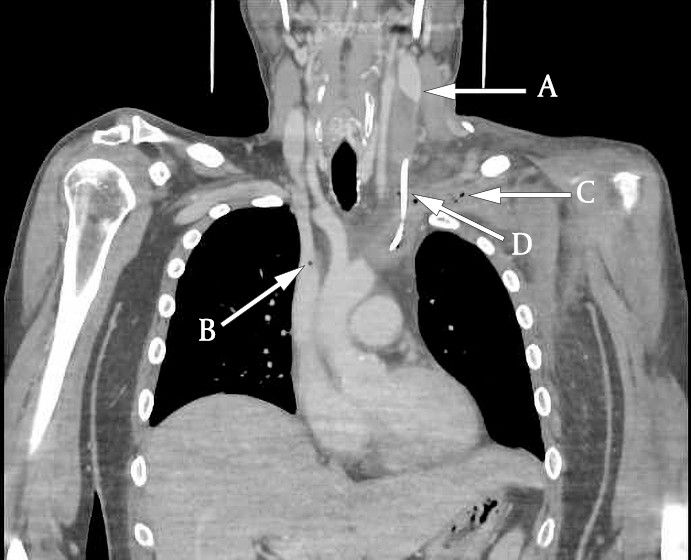

However, ultrasound examination of the neck showed a significant thrombotic mass that almost completely occluded the left internal jugular vein and subclavian vein (Figures 1 and 2). The total extent of the thrombus could not be determined using ultrasound, and therefore CT venography was performed in addition. This revealed extensive thrombosis involving the lower part of the left jugular vein (from the level of the carotid bifurcation), subclavian vein and brachiocephalic vein up to the inlet of the superior vena cava (Figure 3). Multiple air bubbles were dispersed throughout the thrombotic mass. We suspected that these were caused by bacteria, and that the thrombus was thus the focus of the patient's infection.

Ultrasound is a non-invasive and cost-effective method for detecting thrombotic masses. Unfortunately, however, it is suboptimal for diagnosing thrombi located deep below the mandible or clavicle. For this reason, CT venography is preferred by many (6). In our case, CT venography allowed us to determine the extent of the thrombotic mass and also revealed the characteristic air bubbles that strengthened suspicion of an infected thrombus.

Findings of small intravenous air bubbles on CT are not abnormal, as small air bubbles may be injected along with the contrast fluid. Air bubbles may also be seen in the portomesenteric venous system as a result of ischaemia or infection. However, air bubbles within a thrombotic mass are rare, and this finding therefore reinforces suspicion of an infected thrombus (7).